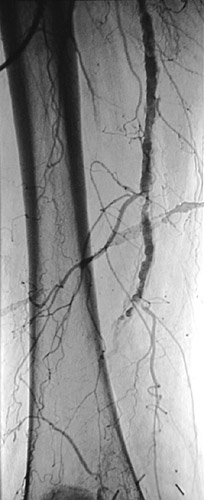

The angiogram seen here demonstrates an area of marked atherosclerotic narrowing involving the distal right femoral artery at the adductor foramen.